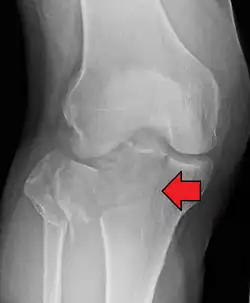

A severe tibial plateau fracture with an associated fibular head fracture

Lateral Tibial Plateau fracture XRay with Depression